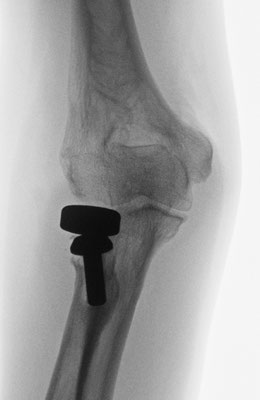

Ellenbogennaher Ellenbruch (Olecranonfraktur)

Der Ellenhaken (Olecranon) stellt den knöchernen Teil dar, über den die Kraft des Trizepsmuskels in den Unterarm geleitet wird und somit die aktive Streckung des Ellenbogens gegen Widerstand ermöglicht wird. Durch den Zug der Trizepssehne wird das kleine Knochenfragment weggezogen. Die Kraftübertragung des Muskels auf den Unterarm ist abgehängt. Insofern ergibt sich die Erfordernis, das Knochenteil und damit auch die Sehne des Trizeps wieder am Unterarm zu befestigen. Zusätzlich muss auch die Kongruenz des Gelenkes wieder hergestellt werden. Je nach dem, ob es sich um einen einfachen oder komplizierten Knochenbruch handelt, wird eine sog. Zuggurtungsosteosynthese mit zwei Drähten und einer Achterschlinge (Abb. 6a-b) oder eine Stabilisierung mit einer Platte durchgeführt.